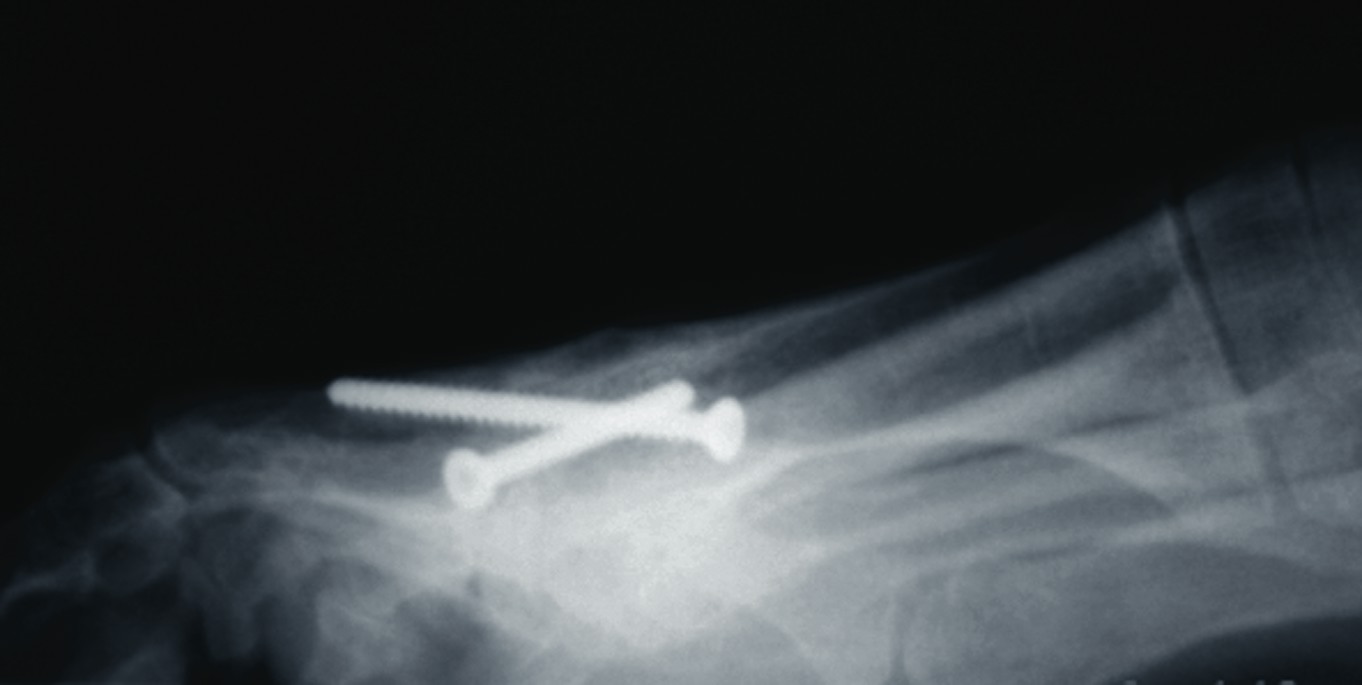

One should place the patient into a supine position and utilize a tourniquet. Evaluate post-anesthesia assessment of the first MPJ range of motion. Manually distract the first MPJ and plantarflex the first metatarsal. Dorsiflex the hallux to determine the obtainable first MPJ range of motion and evaluate for crepitus. If there is first ray hypermobility and no crepitus, one may be able to salvage the first MPJ by translating the first ray plantarly and stabilizing the medial column. Initially, surgeons should address contributing global pathology. Then proceed to the first ray and make a dorsomedial skin incision spanning the first MPJ. Retract the neurovascular structures. Make a longitudinal incision to bone, spanning the distal one-third of the first metatarsal and proximal one-half of the proximal phalanx. Evaluate the adjacent cartilage and make a critical decision to preserve or destroy the joint. It is important to realize that evaluation of cartilage quantity and quality via direct intraoperative visualization weighs heavily upon the final decision to perform a joint preservation or destructive procedure. One should strongly consider joint destructive procedures if greater than 30 percent of the dorsal portion of the first metatarsal head presents as grade III to grade IV chrondromalacia. One must independently evaluate grade III and IV chrondromalacia and osteochondral defects in the remaining 70 percent of the metatarsal head. Small cartilage lesions may yield themselves to debridement, drilling or OATS procedures whereas large cartilage defects will likely result in arthrodesis. If the joint is salvageable and one identifies first metatarsocuneiform hypermobility, perform a cheilectomy and a subsequent, sagittal Lapidus procedure. If one identifies hypermobility or posttraumatic first metatarsal angular pathology, correct it after completing the first MPJ soft tissue and osteophyte debridement. If one decides to perform arthrodesis on the joint, debride identified osteophytes, loose bodies, synovitis and scar tissue. Denude the adjacent cartilaginous surfaces to the healthy level of bleeding bone via curettage or via convex distal and concave proximal reamers. Fenestrate the adjacent bone surfaces with a 1.0- or 1.5-mm drill bit. Temporarily fixate the hallux by utilizing two K-wires in the desired position. The position should be approximately 20 to 30 degrees dorsiflexed in relation to the first metatarsal declination; abducted and parallel to the second digit; and with the nail void of frontal plane varus or valgus rotation. Obtain an AP radiograph to evaluate the bony apposition and alignment of the proposed first MPJ arthrodesis. Also obtain a lateral radiograph with the foot loaded in order to evaluate the hallux and its relationship to the first ray. After obtaining the desired position, utilize two fully threaded (3.5 or 4.0) crossing cortical screws for permanent fixation. Place the first screw from proximal medial to distal lateral and place the second screw from distal medial to proximal lateral across the first MPJ. Ensure the screws do not cross at the level of the joint. Use a 3.5-mm burr to create a dell in the cortical bone where the head of the screws engage the bone as Manloli and Hansen have described.48 After obtaining rigid internal fixation across the first MPJ, utilize a shear strain autograft (harvested via a percutaneous calcaneal grafting technique) at the arthrodesis site.57 Place the autograft in two troughs created by the 3.5-mm burr at the arthrodesis site. Use a bone mallet and tamp to provide a press fit.58